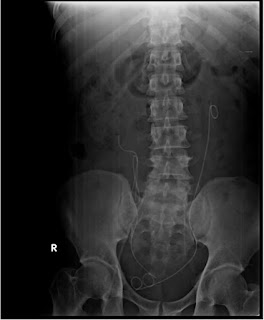

Investigations:

On admission

19.5.22